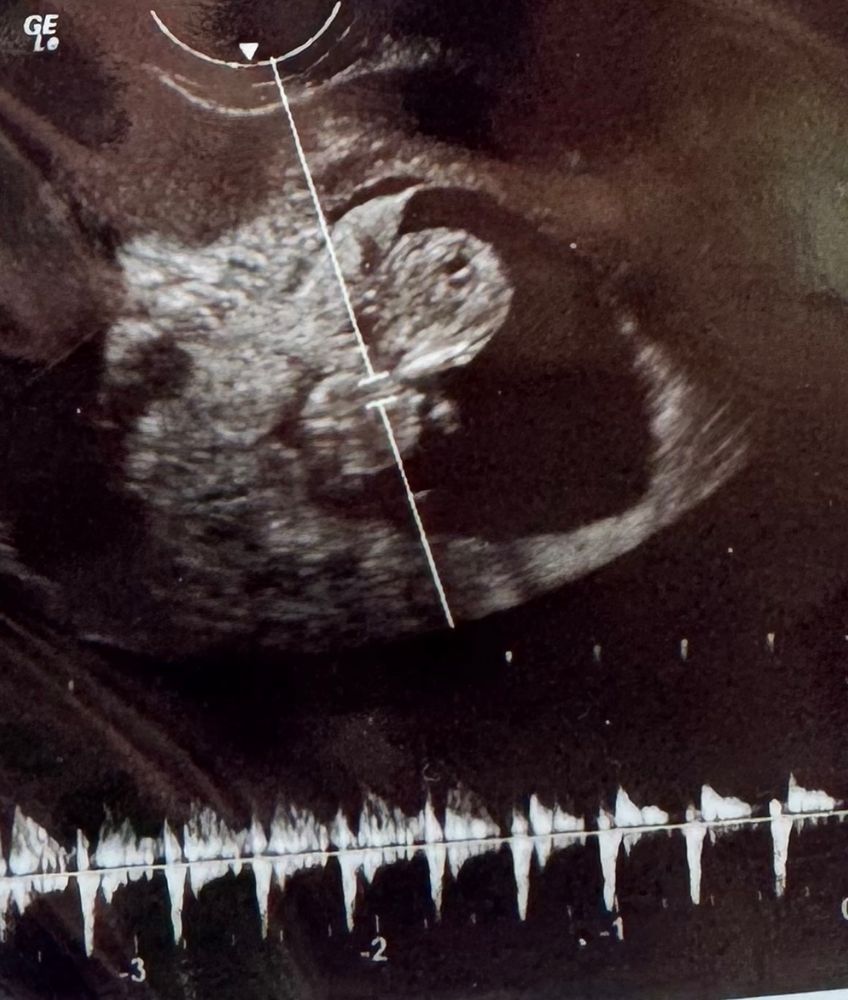

Мы с мужем пошли внепланово на платное узи в 10 недель, муж впервые увидел нашу малышку) у нее уже были ручки, ножки, головка, такая милашка)) сделали нам пару фоток, мы вышли, я сразу сделала фото и поехали каждый на свою работу. Как же я удивилась, когда через 2 часа моя мама присылает мне фото своей кофейной гущи и пишет: Что ты видишь? Кажется мы кого-то ждём? 😱

Ниже фото того узи в 10 недель и маминой гущи